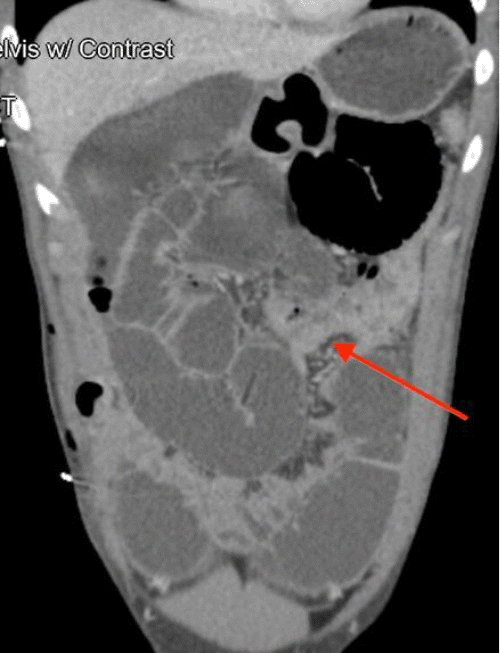

Contrast-enhanced CT scan of the abdomen and pelvis revealed findings consistent with mechanical obstruction. A transition point abutting the abdominal wall at the prior projectile injury site was noted proximal to the ileocolic anastomosis (Figure 3). A small bowel follow-through demonstrated small amounts of contrast in the distal small bowel loops at an 8-hour delay, indicating possible incomplete obstruction (Figure 4). Following discussion with the patient and guardian, a decision was made to perform a re-exploratory laparotomy.

Figure 3. CT Depicting Mechanical Small Bowel Obstruction at Prior Injury Site. Published with Permission

Axial view demonstrating the transition point abutting the fascial defect in the abdominal wall

(B) Axial view showing the collapsed bowel originating proximal to the ileocolic anastomosis (blue arrow)

(C) Axial view  of the ileocolic anastomosis (green arrow)